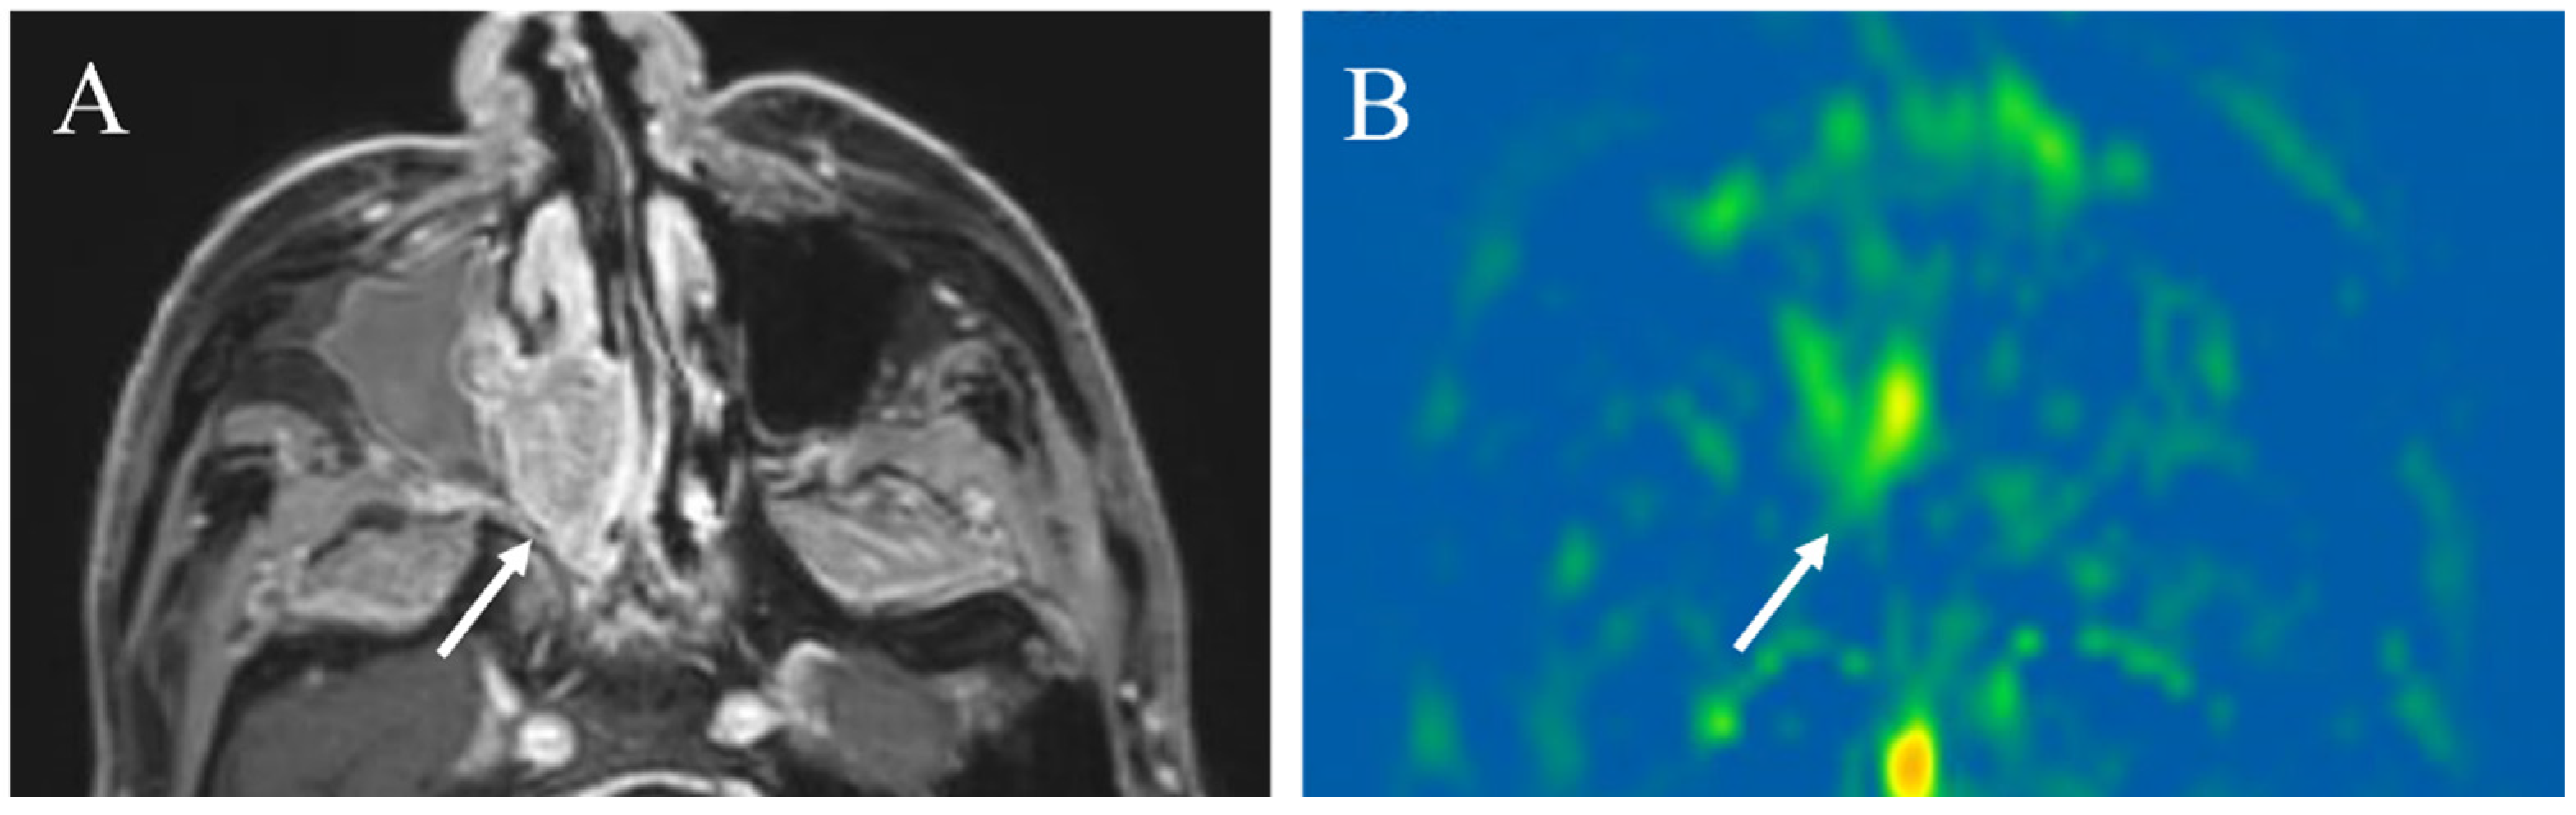

Figure 9. A 72-year-old male with acinic cell carcinoma of the right parotid gland: (A) STIR shows a mass with high signal intensity (arrow); (B) ADC map shows mild restricted diffusion (arrow) (ADC 10th percentile, 0.93 × 10−3 mm2/s and ADC mean of 1.03 × 10−3 mm2/s); (C) pCASL image shows high TBF (arrow) (TBF 50th percentile, 34.26 mL/100 g/min).